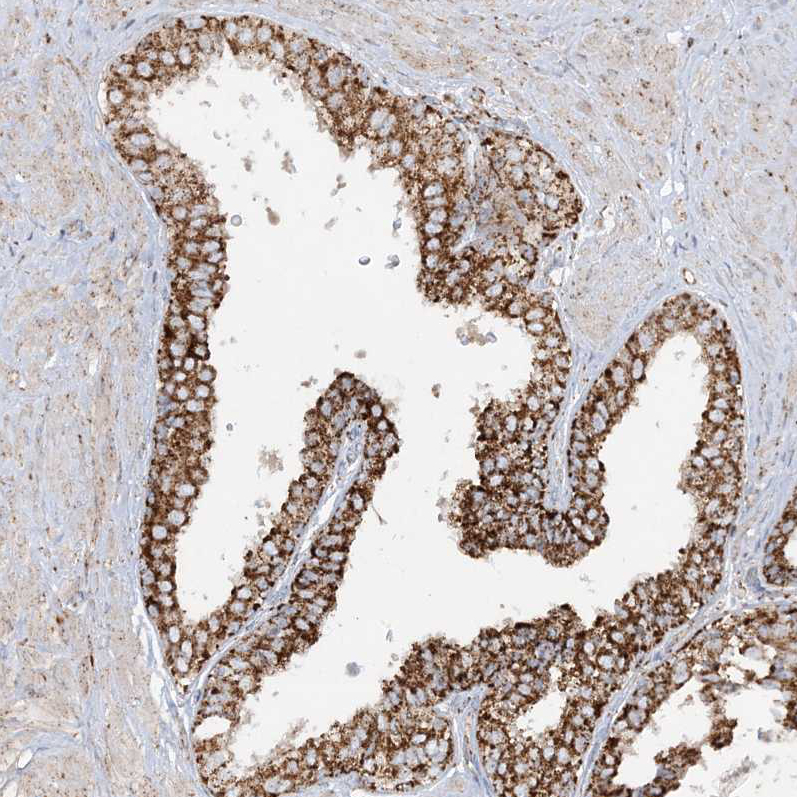

Immunohistochemical staining of human fallopian tube, kidney, prostate and testis using Anti-NDUFAF3 antibody HPA035376 (A) shows similar protein distribution across tissues to independent antibody HPA035377 (B).